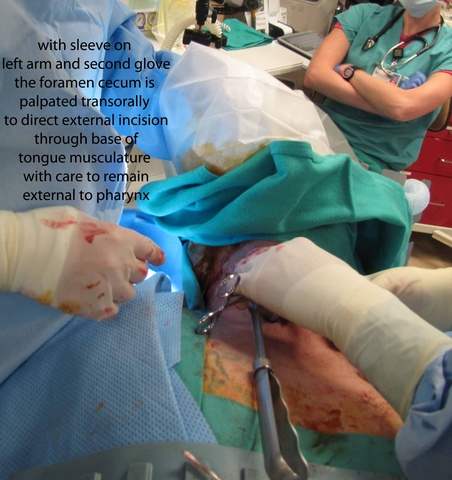

From above, surgeon reached into the mouth and palpated the foramen cecum with the left hand and arm protected with a sterile sleeve and second glove - placed to permit later removal from the contaminated oral cavity to permit continued sterile dissection in a sterile field. With anatomic control directed by palpation intra-orally with concurrent dissection of the open neck, clips were placed to mark the region of the undersurface of the base of tongue where the TGD cyst was to be severed. Final cuts with the bovie were similarly directed both by intra-oral palpation and extra-oral inspection.